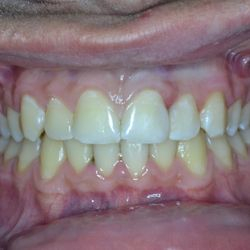

Η νεαρή αυτή ασθενής προσήλθε στο ιατρείο παραπονούμενη για την εμφάνιση των τεσσάρων άνω τομέων της.

Τα δόντια είχαν με την πάροδο των ετών σπάσει στην κοπτική τους επιφάνεια και το φαινόμενο αυτό επιδεινώνονταν σταδιακά με απώλεια όλο και περισσότερης οδοντικής ουσίας.

Αποφασίστηκε να αποκατασταθεί η δομική ακεραιότητα των δοντιών αυτών με χρήση σύνθετης ρητίνης νανουβριδικής τεχνολογίας (Herculite XVR Ultra/Kerr).

Η αποκατάσταση τους έγινε σε ένα ραντεβού και το αισθητικό αποτέλεσμα ικανοποίησε στο ακέραιο τις προσδοκίες της ασθενούς μας.